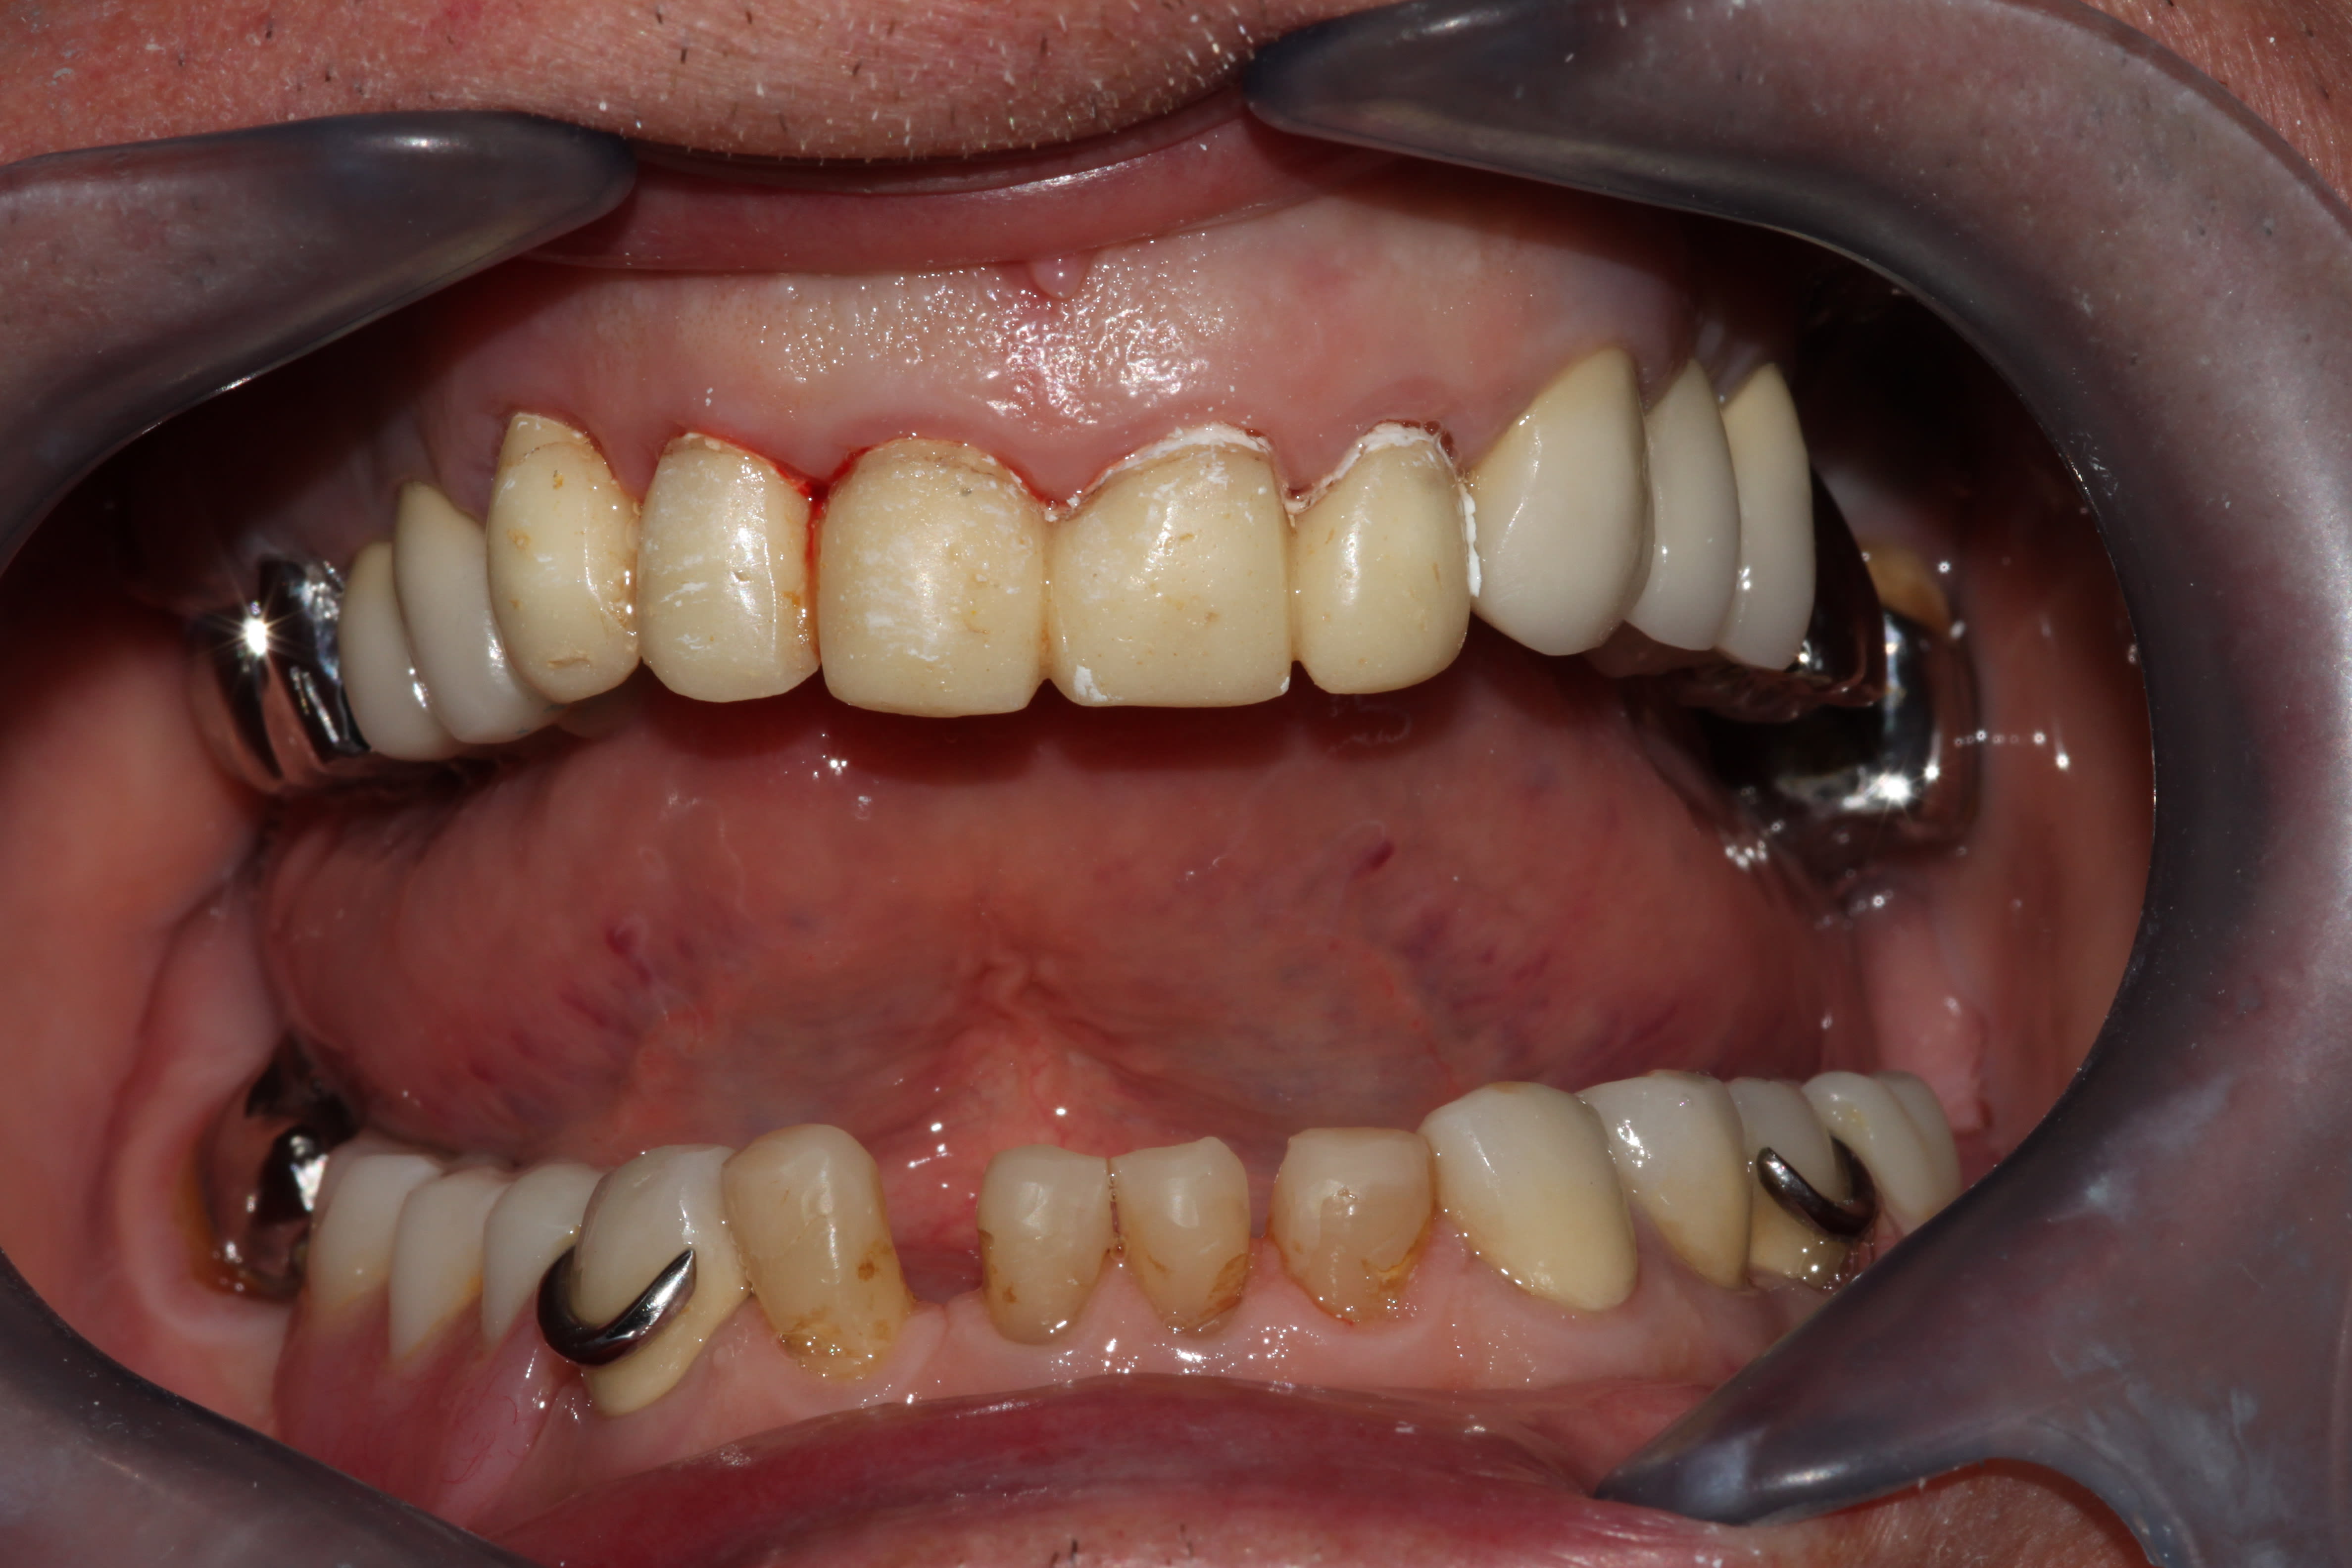

J'avais eu un boulot comme ça, probablement, le plus compliqué que j'ai jamais eu à gérer, les dents à ras la gencive genre attaque chimique interdite par la convention de Genève, et dv parfaitement conservée. Les incisives mandibulaires avaient fini à la benne pour faire de la place.

Edit: a y est j'ai retrouvé. Même l'endo avait été une chierie sans nom, toutes calcifiées, toutes les mono-radiculées avaient 2 canaux distincts, j'avais perforé la 45 en tirant de travers...

Img 4061 ru6pto - Eugenol

Img 4178 fcvnew - Eugenol

Boooo .on reconnait ta signature , tu avais posté un meme genre de sourire dans :

Sethef

Ce boulot date de 2 ans je crois. Pas retrouvé celui auquel tu penses, mais j'imagine que ça doit plus être le style du prothésiste que le mien.

J'y ai pensé parce que j'ai revu le patient aujourd'hui, je m'occupe de son épouse maintenant. Stellites en place depuis 23 ans, "un peu" enfoncés. Donc vestibulo version des antérieures restantes bien sûr. C'est plus simple, elle j'ai pu lui remonter sa dv haha.